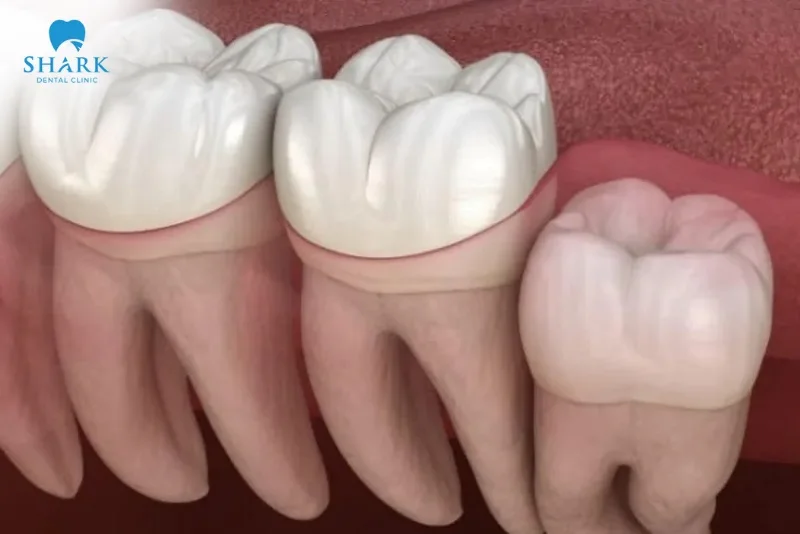

- Răng khôn mọc lệch đâm vào răng số 7: Đây là dạng mọc lệch nguy hiểm, làm tổn thương răng số 7, tạo kẽ sâu và tăng nguy cơ mất răng hàm quan trọng.